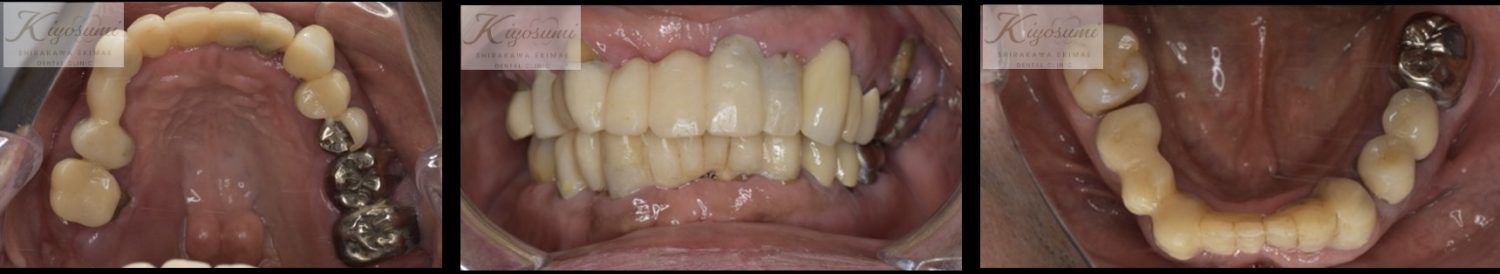

| 主訴 | 歯が揺れて噛めないので、噛めるようにして欲しい。 |

| 治療内容 | 基本的な歯周病治療、根の治療を実施し、歯の高さが足りない箇所は歯冠長延長術、保存が難しい歯は一部歯根分割抜去を行いました。欠損部はインプラントを用いず、ジルコニアブリッジで仕上げています。 |

| 想定されたリスク | ※残存している歯の本数が少ないため、残っている歯だけでブリッジを行うには長期予後が見込めない可能性があり、患者さんにご理解をいただいたうえで被せ物を行っています。 ※歯周病治療や根の治療をしても歯を残せない可能性がありました。 |